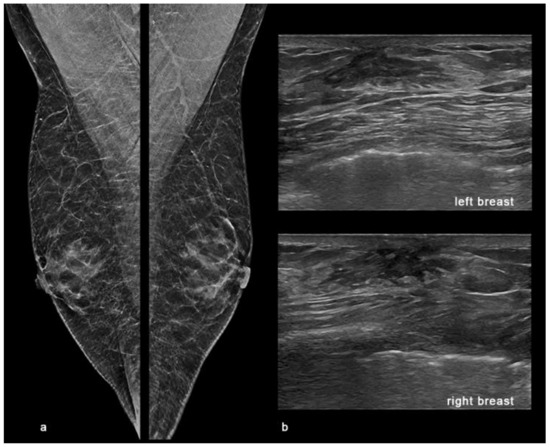

2. Case Report